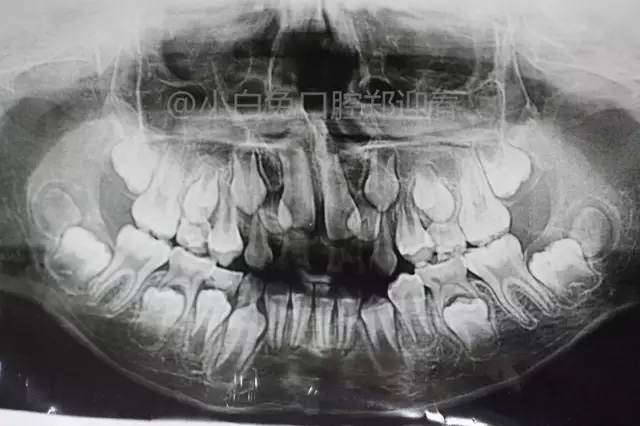

患兒,10歲,因上前牙未替換來診,查體:輕度反合,51和52、61和62均融合,且存在間隙約4mm,全面曲面斷層片顯示:11、21未萌,52、51、61、62牙根均有不同程度的生理性吸收。